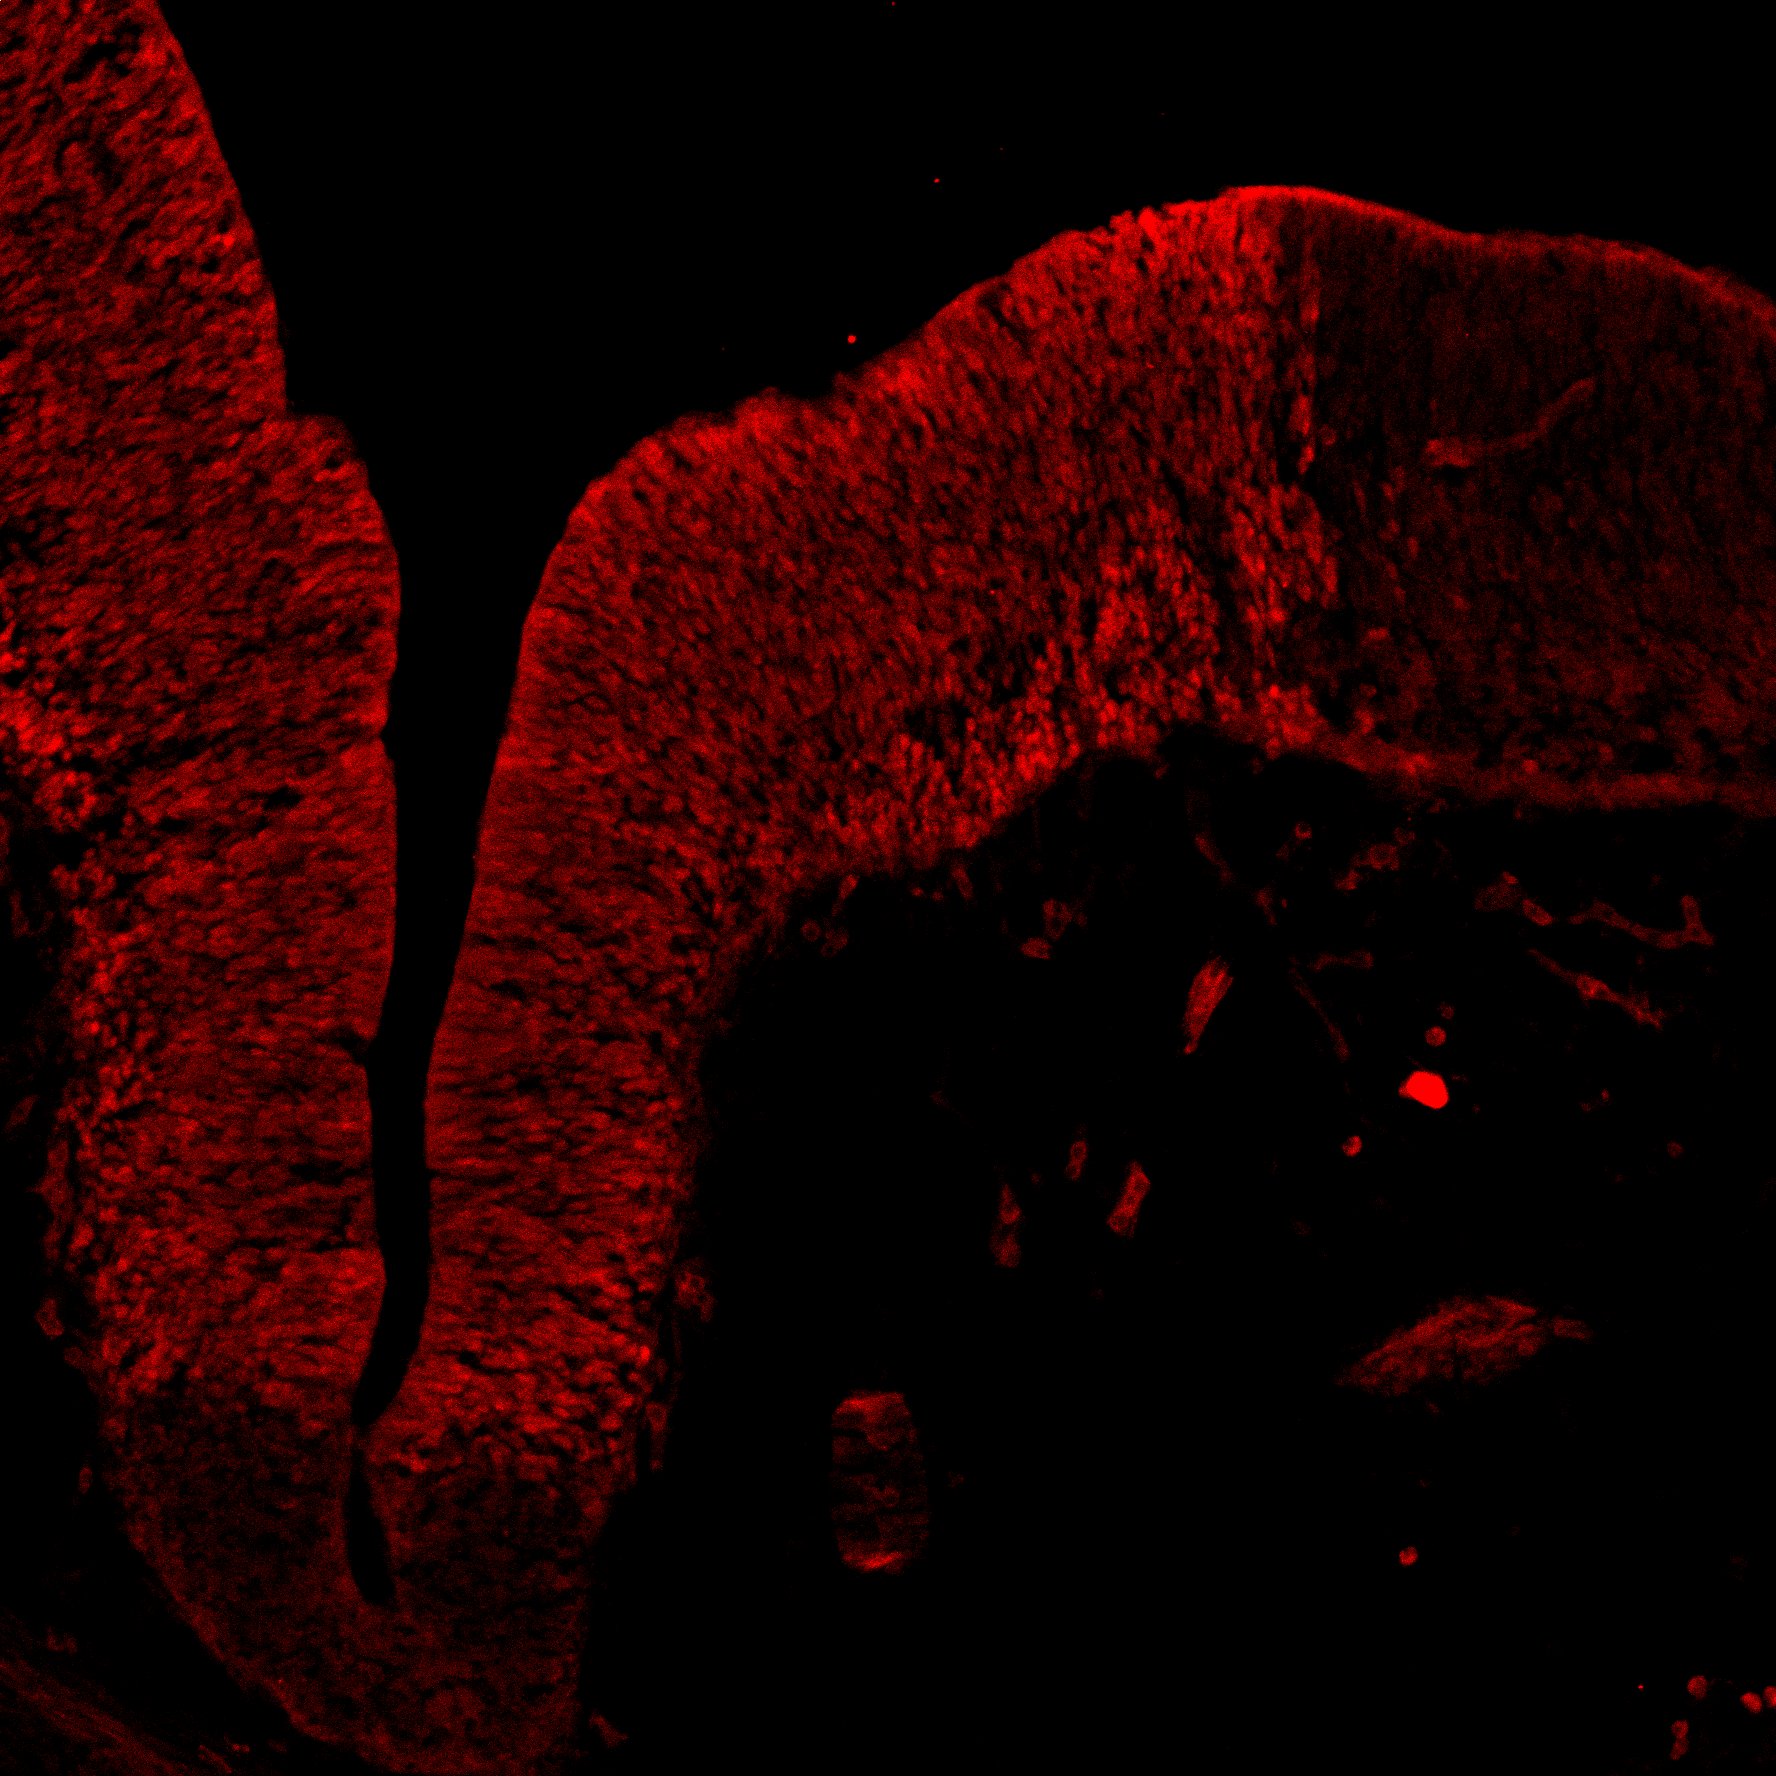

An in vivo and in vitro spatiotemporal profile of human midbrain development

An anatomical analysis of the developing human midbrain from 6 post-conceptional weeks (PCW) to 22 PCW reveals increased tissue complexity, characterized by the emergence of dopaminergic nuclei, as highlighted by immunofluorescence analysis for tyrosine hydroxylase (TH).

DAPI

11PCW human midbrain

MAP2

TH

Merged